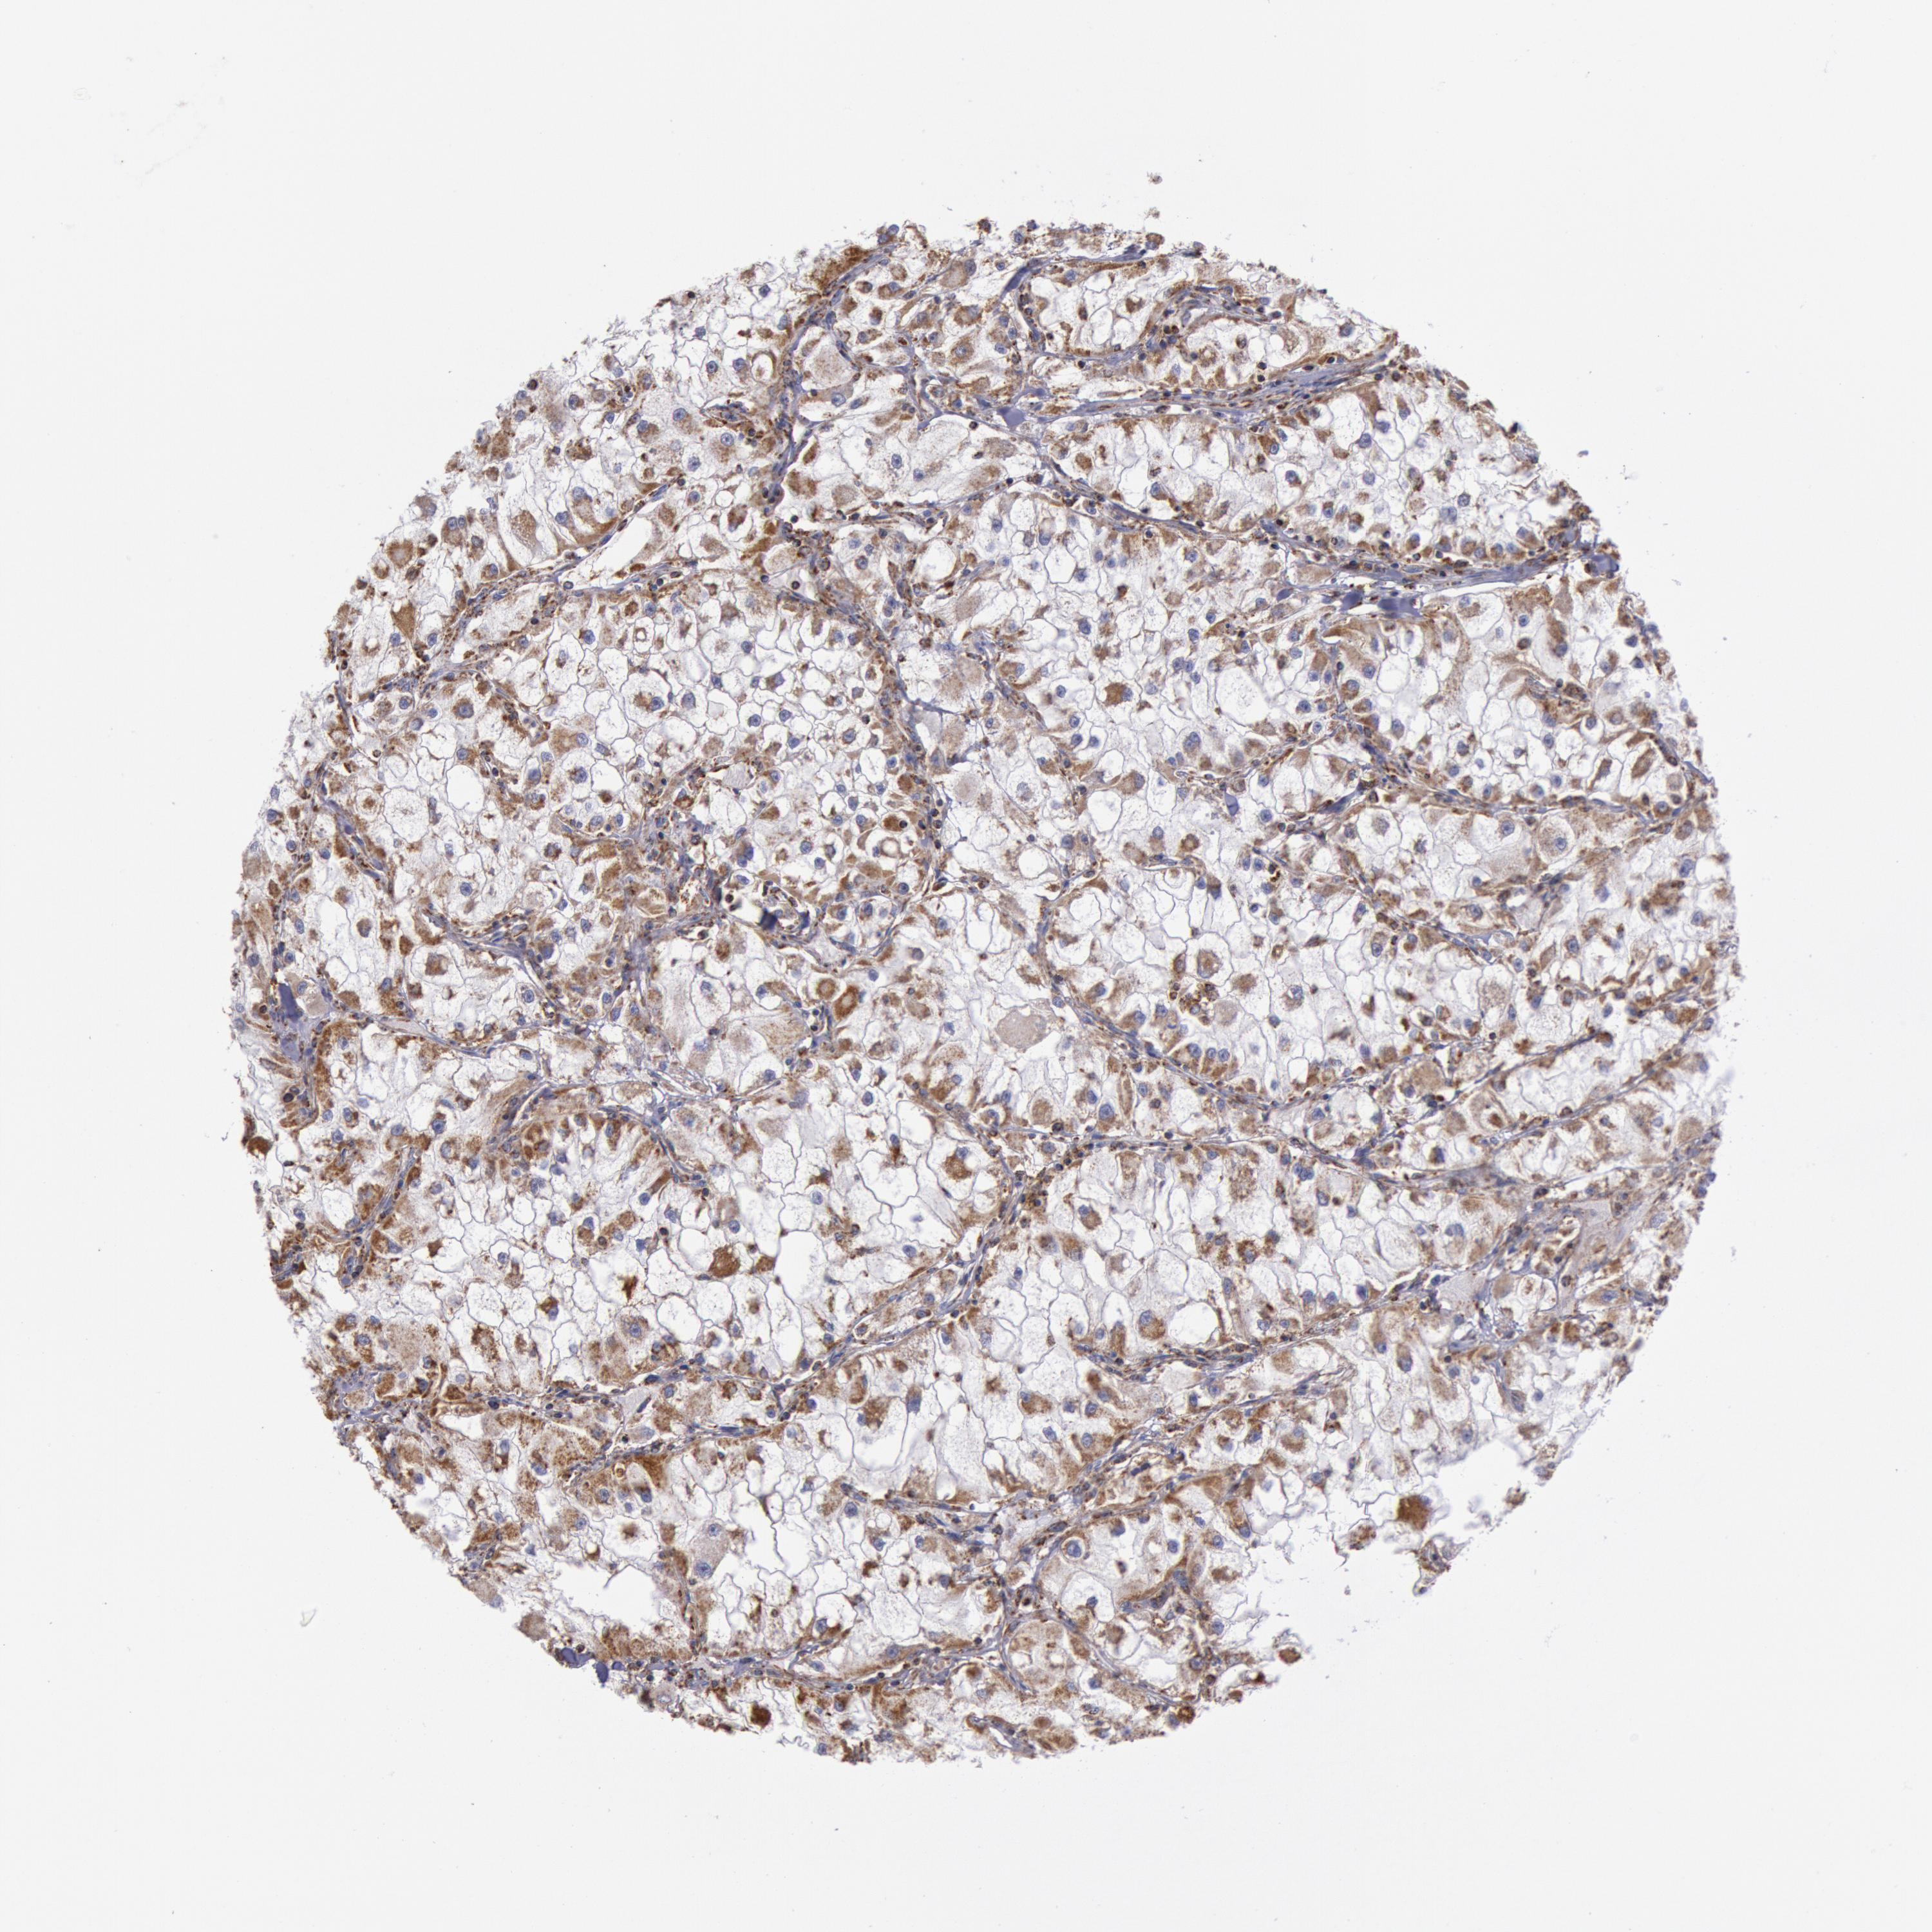

CANCER RENAL CANCER Show tissue menu

KICH TCGA KIRC TCGA KIRC VALIDATION KIRP TCGA PROTEIN RCC CPTAC PROTEIN EXPRESSION